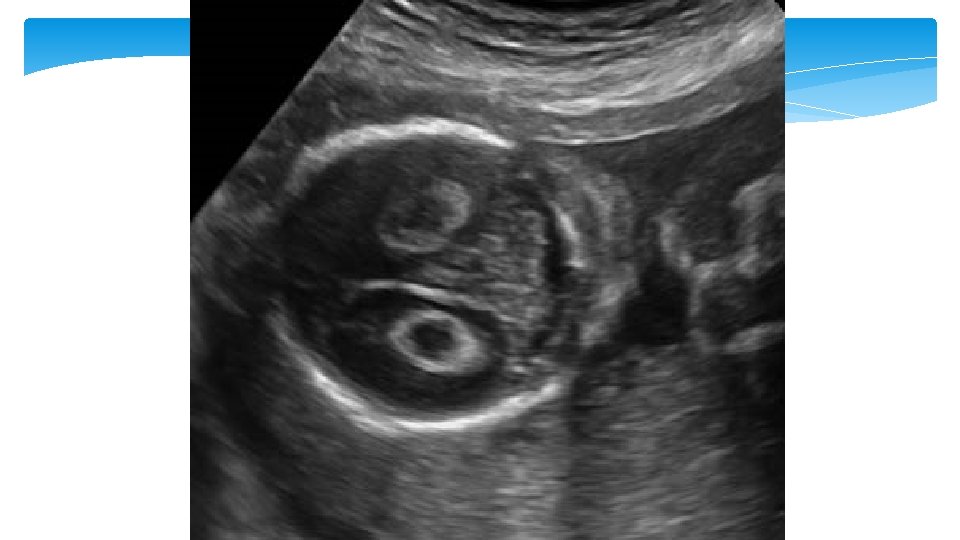

Echogenic focus (EF) of the heart An is definced as an echogenic area located in the region of the papillary muscles but not attached to the ventricular walls. They move with the atrioventricular valve and can occur in either cardiac ventricle, but are mainly seen in the left ventricle EF are seen in approximately 4% of obstetric sonograms with the lowest prevalence in Black populations and highest rates seen in Asian women

Soft marker Imaging criteria Echogenic tissue in one Second trimester: or both ventricles of the echogenic heart seen on standard intracardiac foci four-chamber view Aneuploidy association • LR 1. 4 to 1. 8 for Down syndrome • Seen in 15 to 30% of Down syndrome and 4 to 7% euploid fetuses Renal pelvis measuring ≥ 4 Second trimester: mm in anteroposterior • LR 1. 5 to 1. 6 for Down pyelectasis diameter up to 20 weeks syndrome of gestation Second trimester: Fetal small bowel as echogenic bowel echogenic as bone • LR 5. 5 to 6. 7 for Down syndrome • Associated with aneuploidy, intra-amniotic bleeding, CF, CMV Management 1. If isolated finding, aneuploidy screening should be offered if not done previously 2. If aneuploidy screen result is negative, no further evaluation is required 1. If isolated finding, aneuploidy screening should be offered if not performed previously 2. Repeat ultrasonography in third trimester for potential urinary tract obstruction 1. Further counseling 2. Offer CMV, CF, and aneuploidy screening or diagnostic testing